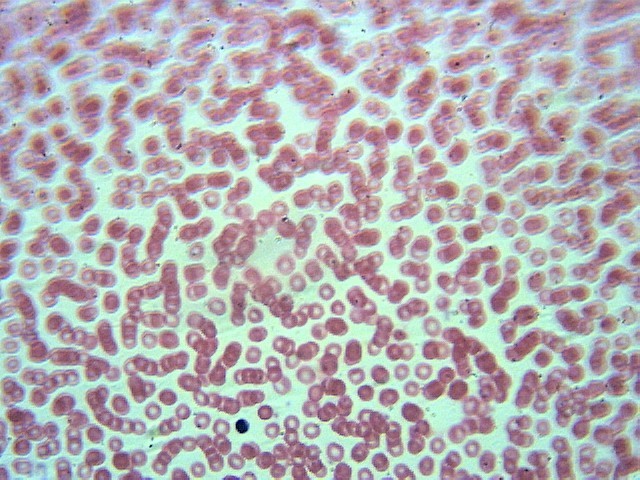

Кровь человека - 10 шт.